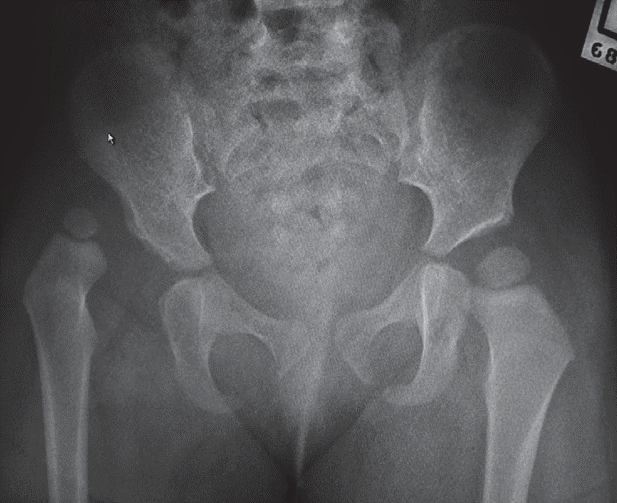

Hip fracture

Overview

Hip fractures are rare in children. They usually occur from high-energy trauma, particularly MVA and a high index of suspicion is needed to diagnose them. X-ray (AP and lateral views) are essential to make the diagnosis, and a CT scan may be indicated for occult fractures. Below is a table summarising how hip fractures are classified.

Hip dislocation

Posterior dislocations account for 80% of hip traumas. Low energy injuries cause traumatic hip dislocations in the younger child (2–5 years) due to associated ligamentous laxity. In older children (11–15years), dislocated hips are caused by higher energy injuries and have a higher association with acetabular fractures, although this is rare. Dislocations are more common than fractures in the paediatric population.